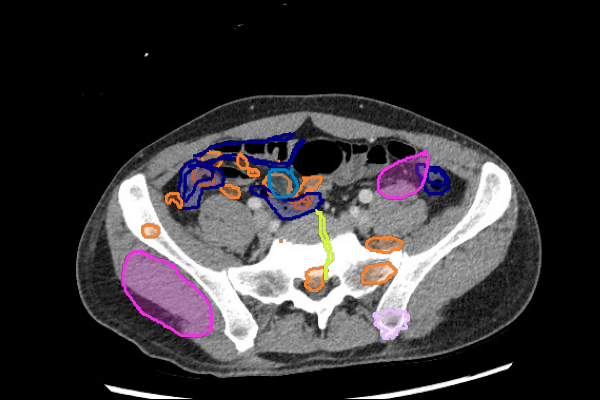

- Masses in the mesentery/peritoneum are often overlooked. Take advantage of multiplanar imaging and look in characteristic locations for peritoneal lesions.

- Look for filling defects in the vessels. Venous enlargement might indicate acute thrombus and confirming increased density by applying tight windows to potentially detect acute venous thrombus can be useful.

Mass or Adenopathy

Stones